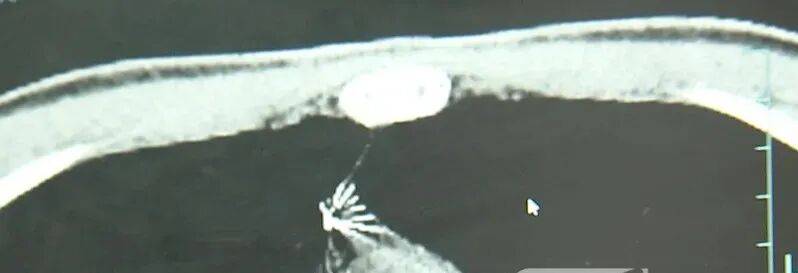

近日,安徽17岁小伙小陆参加征兵体检,胸片结果显示:胸腔内有一处金属高密度影,形态细长,像一根针互联网投资理财。

进一步的CT检查确认,异物是一枚金属针,斜插在肺组织内,位置十分凶险互联网投资理财。

杭州市第一人民医院心胸外科副主任冯兴说:“我们看到这个针的尖锐部,正好指向他体内的一个大血管,边上是上腔静脉和胸主动脉,因此这个针稍有不慎,就有可能造成周边血管的损伤,甚至危及生命互联网投资理财。”